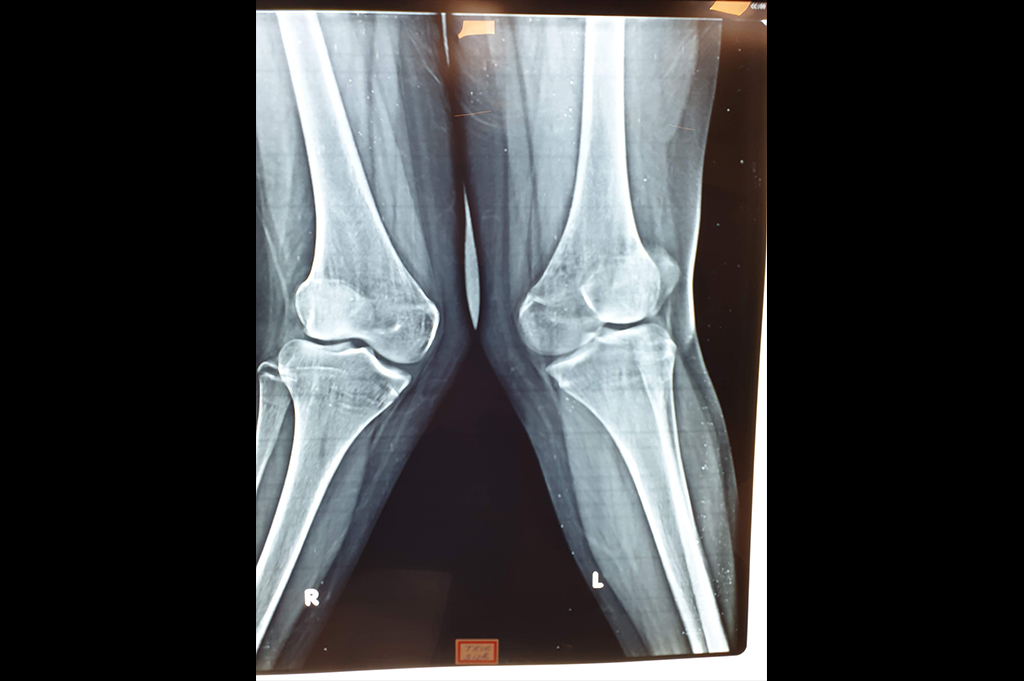

Osteoarthritis – High Tibial Osteotomy - HTO

Deformity Correction - Genu Valgum